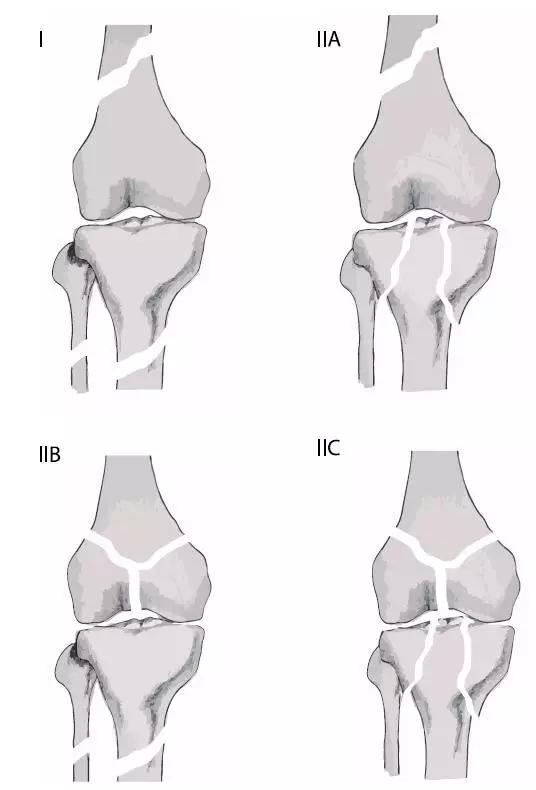

浮膝的 Fraser's 分型(来源:Management of the Floating Knee in Polytrauma Patients. Open Orthop J. 2015 Jul 31;9:347-55.)